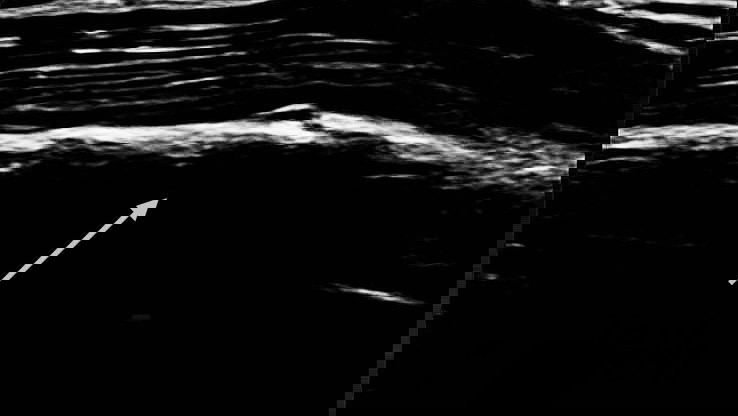

One of the attached images included an X-ray showing a rib fracture to his sixth rib.

The image was dated Monday July 8, which was the morning after the British Grand Prix. Piastri finished fourth in the Silverstone race.

Given the timing of the X-ray, it suggests the 23-year-old Australian was still in some discomfort when he claimed his maiden F1 victory at the Hungarian Grand Prix, which took place two weeks later.